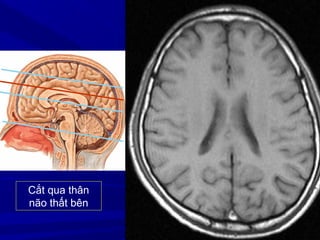

Cắt qua não thất IV

Cắt qua não thất III

Cắt qua thân

não thất bên

Cắt qua trên